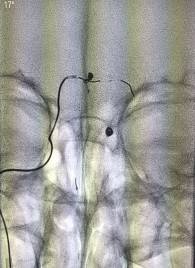

再次行左侧股动脉穿刺,引入另一根指引导管进入右侧颈内动脉,将一根Prowler Select Plus支架导管通过右侧颈内动脉、后交通动脉、右侧大脑后动脉到达左侧大脑后动脉P2段。再将SL-10微导管通过置入左侧椎动脉的另一根指引导管到达动脉瘤腔,选择Enterprise 4.5mmx14cm支架跨瘤颈放置,采用半释放技术,选择一枚Delta paq 1.5mmx4cm栓塞动脉瘤两个瘤囊。

动脉瘤填塞完毕后,完全释放支架保护瘤颈。